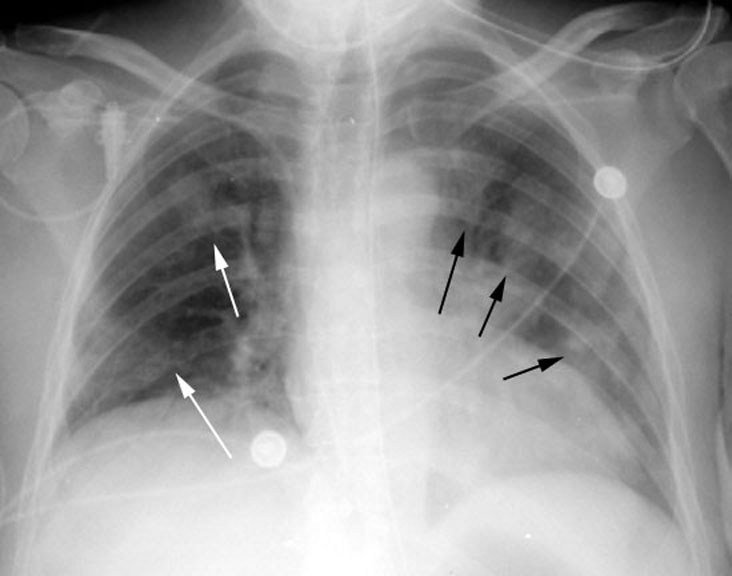

Фотографии заболеваний бронхолегочной системы